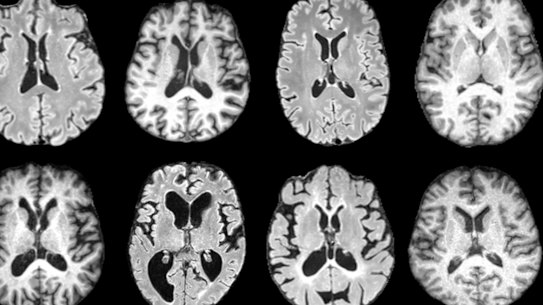

In the first paragraph of the “Overview” was a snippet of information that I’d never seen. The term dementia covered “impaired thinking, remembering or reasoning that can affect a person’s ability to function safely”. And then came this remarkable statement: “the term has been replaced by ‘major neurocognitive disorder’ and ‘mild cognitive disorder’ in medical terminology”. Nonetheless, and disappointingly, the rest of the article repeatedly reverted to dementia while describing its variety of types, and of different and progressive symptoms, rather than using the far less emotive medical terminology.